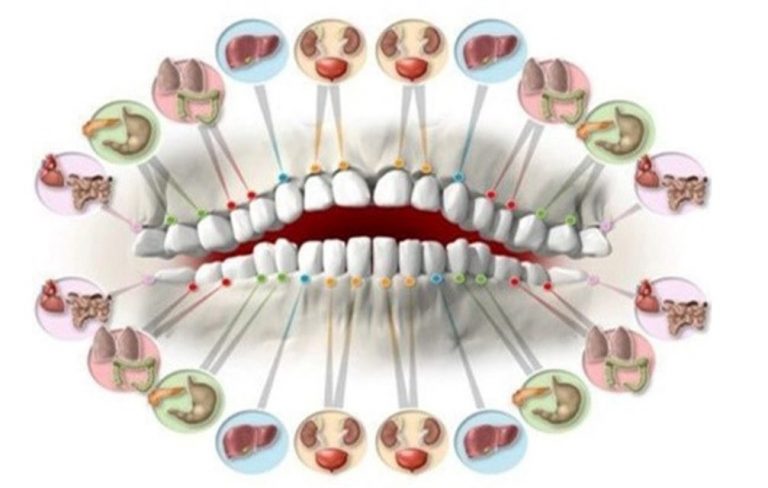

A boca desempenha importantes funções que repercutem na saúde do organismo como um todo. Além de exercer papel fundamental na fala, na mastigação e na respiração, a boca é a maior cavidade do corpo a ter contato direto com o meio ambiente, sendo a porta de entrada para bactérias e outros microrganismos.